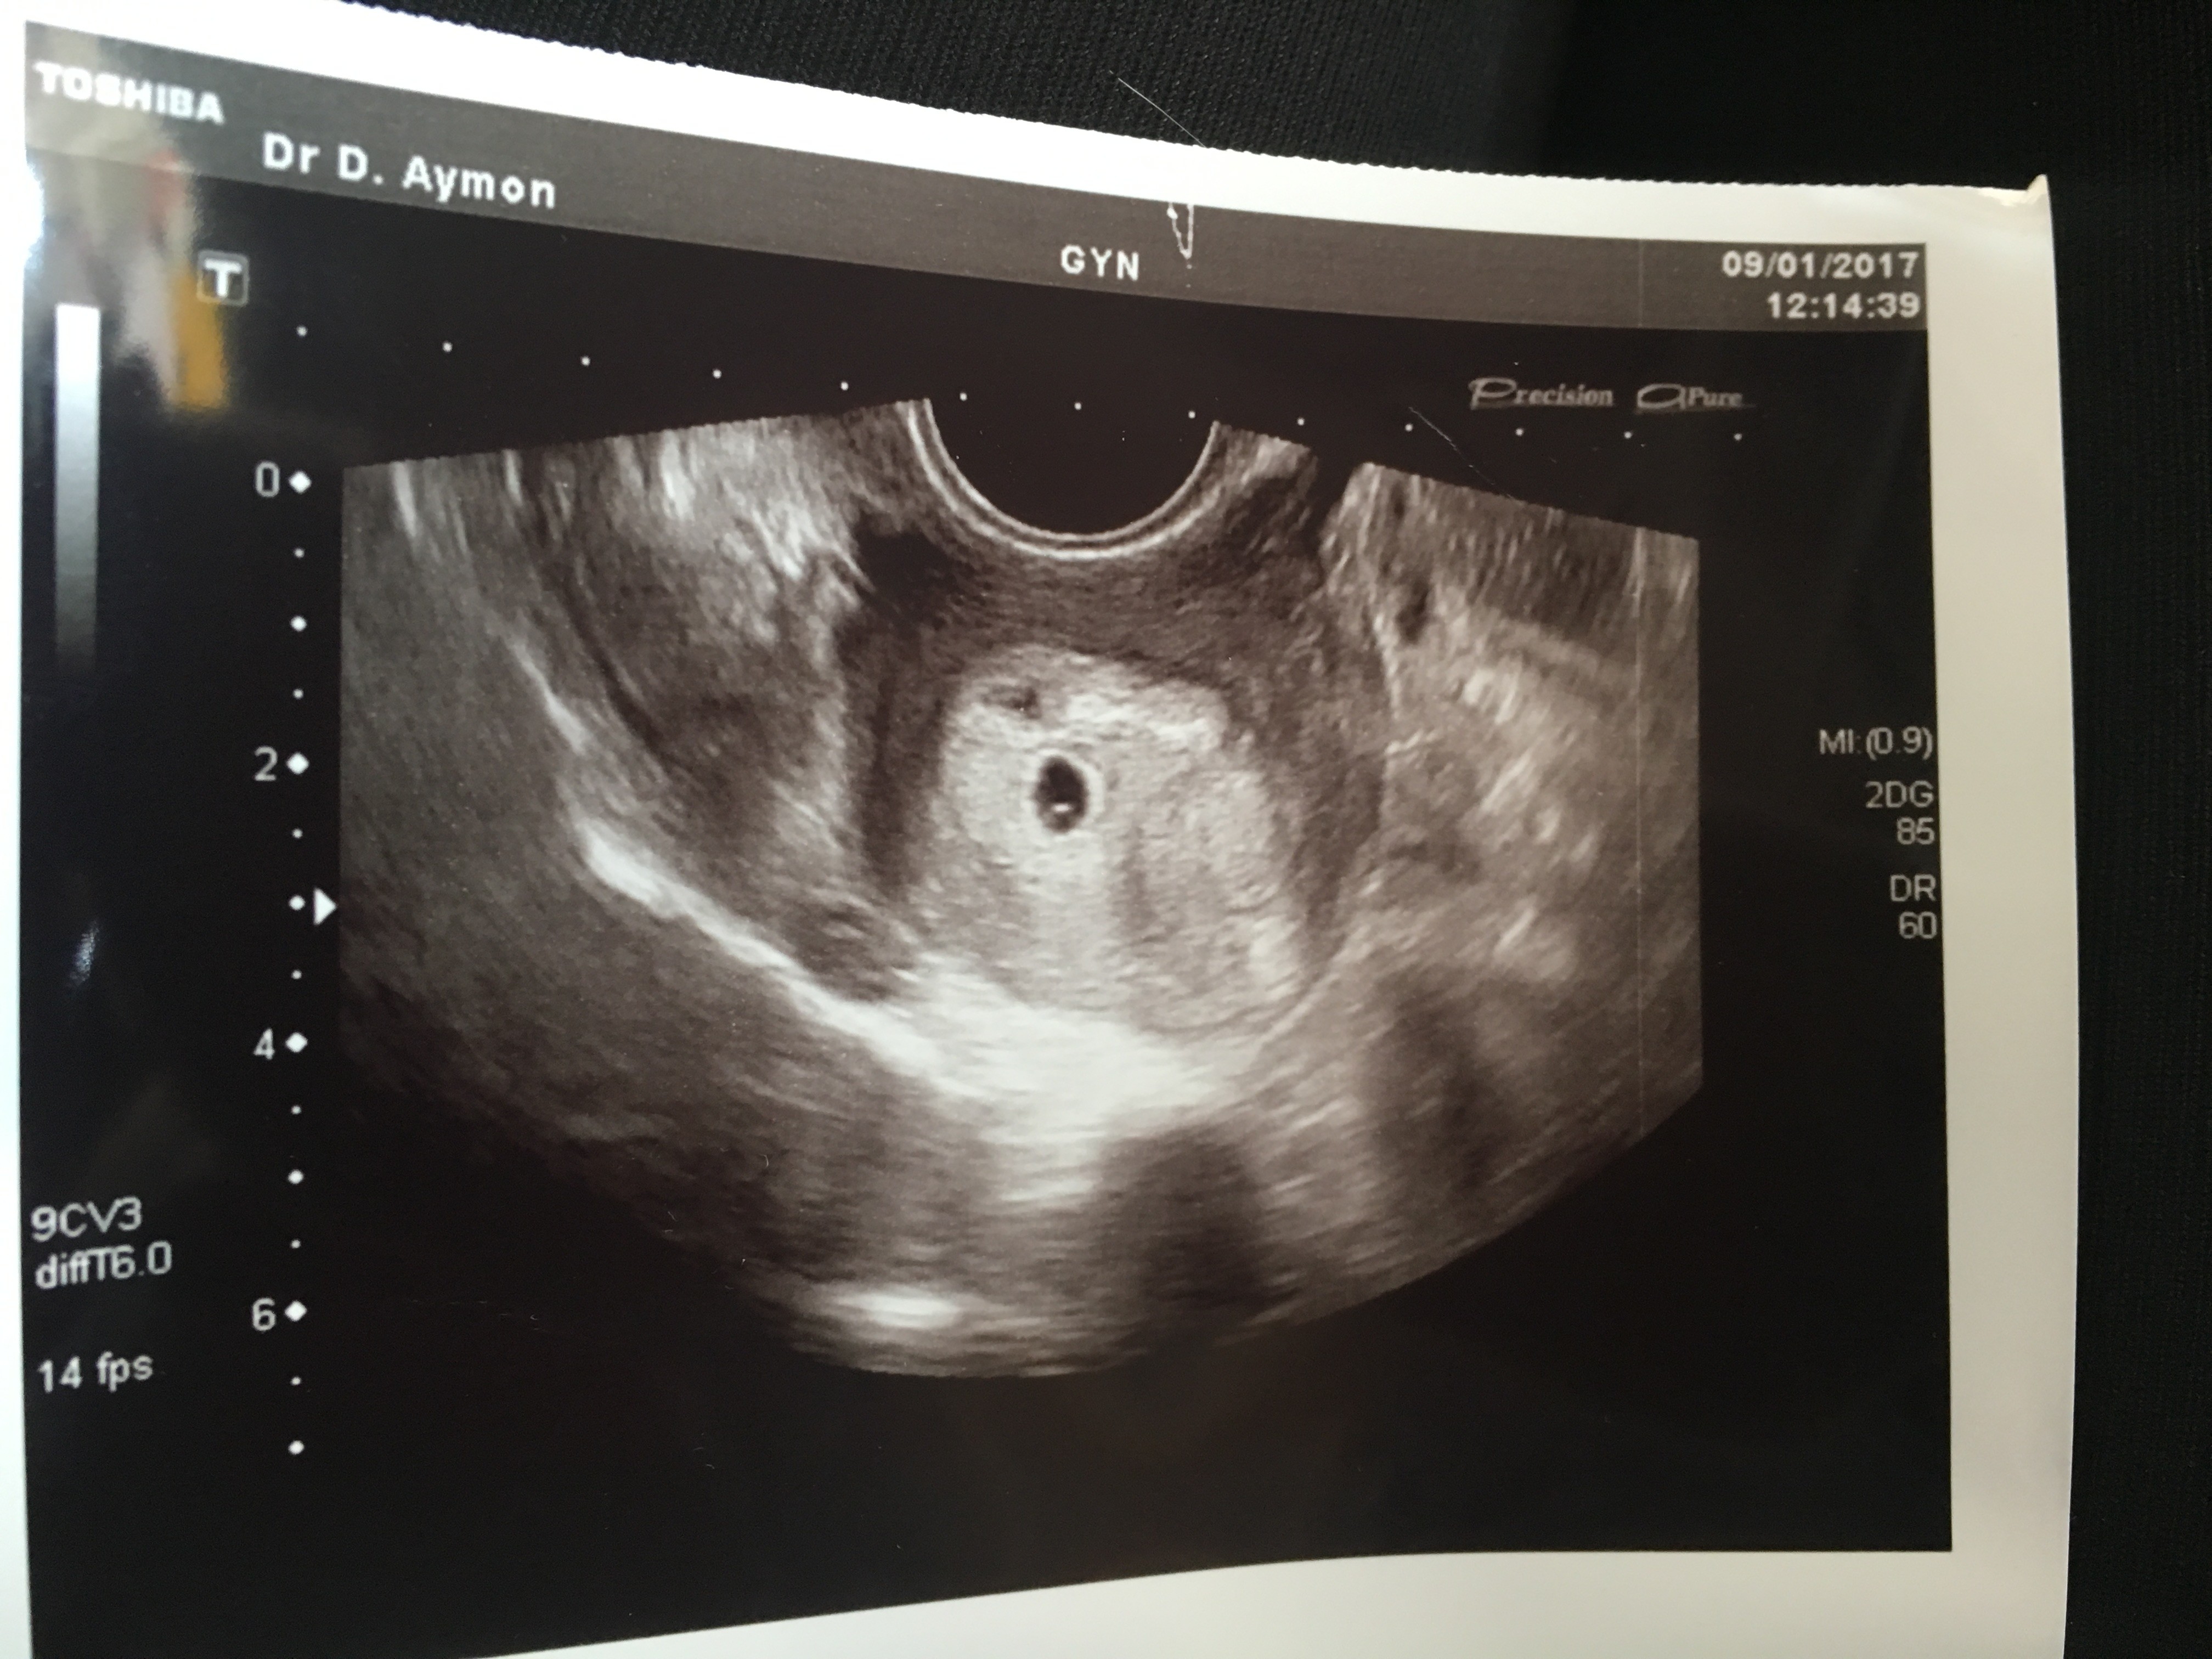

Echographie Grossesse Non Evolutive

Trois échographies de dépistage sont recommandées aux femmes enceintes à chaque trimestre de la grossesse. Dans le cas d’une grossesse intra utérine d’évolution incertaine (sac gestationnel intra-utérin < 25 mm) sans vésicule vitelline visible, l’absence d’apparition d’un embryon avec une activité cardiaque à l’échographie endovaginale dans un délai d’au moins 14 jours permet d’affirmer que la grossesse est arrêtée (Grade C). Il mesure alors 2 à 3 mm.L'utilisation de la voie endovaginale est souvent nécessaire pour le voir.

Pour les oeufs clairs (grossesse non évolutive) l'expulsion se fait généralement naturellement (règles presques normales), on controle parfois par une échographie que l'utérus est bien vide et si ce n'est pas le cas on peut procéder à un curetage. La gynéco confirme mes doutes, elle me dit que l’embryon a 1 mois de retard par rapport au terme calculé depuis mes dernières règles. Mon sac gestationnel est 14 mm et l'embryon serait de 2 mm.

Pour mettre en évidence l'arrêt d'une grossesse, le gynécologue doit procéder à une échographie endo-vaginale (la sonde est insérée dans le vagin de la patiente), plus précise qu'une échographie abdominale. IVG suite a une grossesse non évolutive. Entre 0,5 et 1 % (5).

Mais le risque d'une grossesse non développée au troisième trimestre reste encore. écho et la poche messure 23 mm pour elle et vide pas d’embryon, elle me reconfirme grossesse non evolutive. Il ne comporte pas d'embryon.